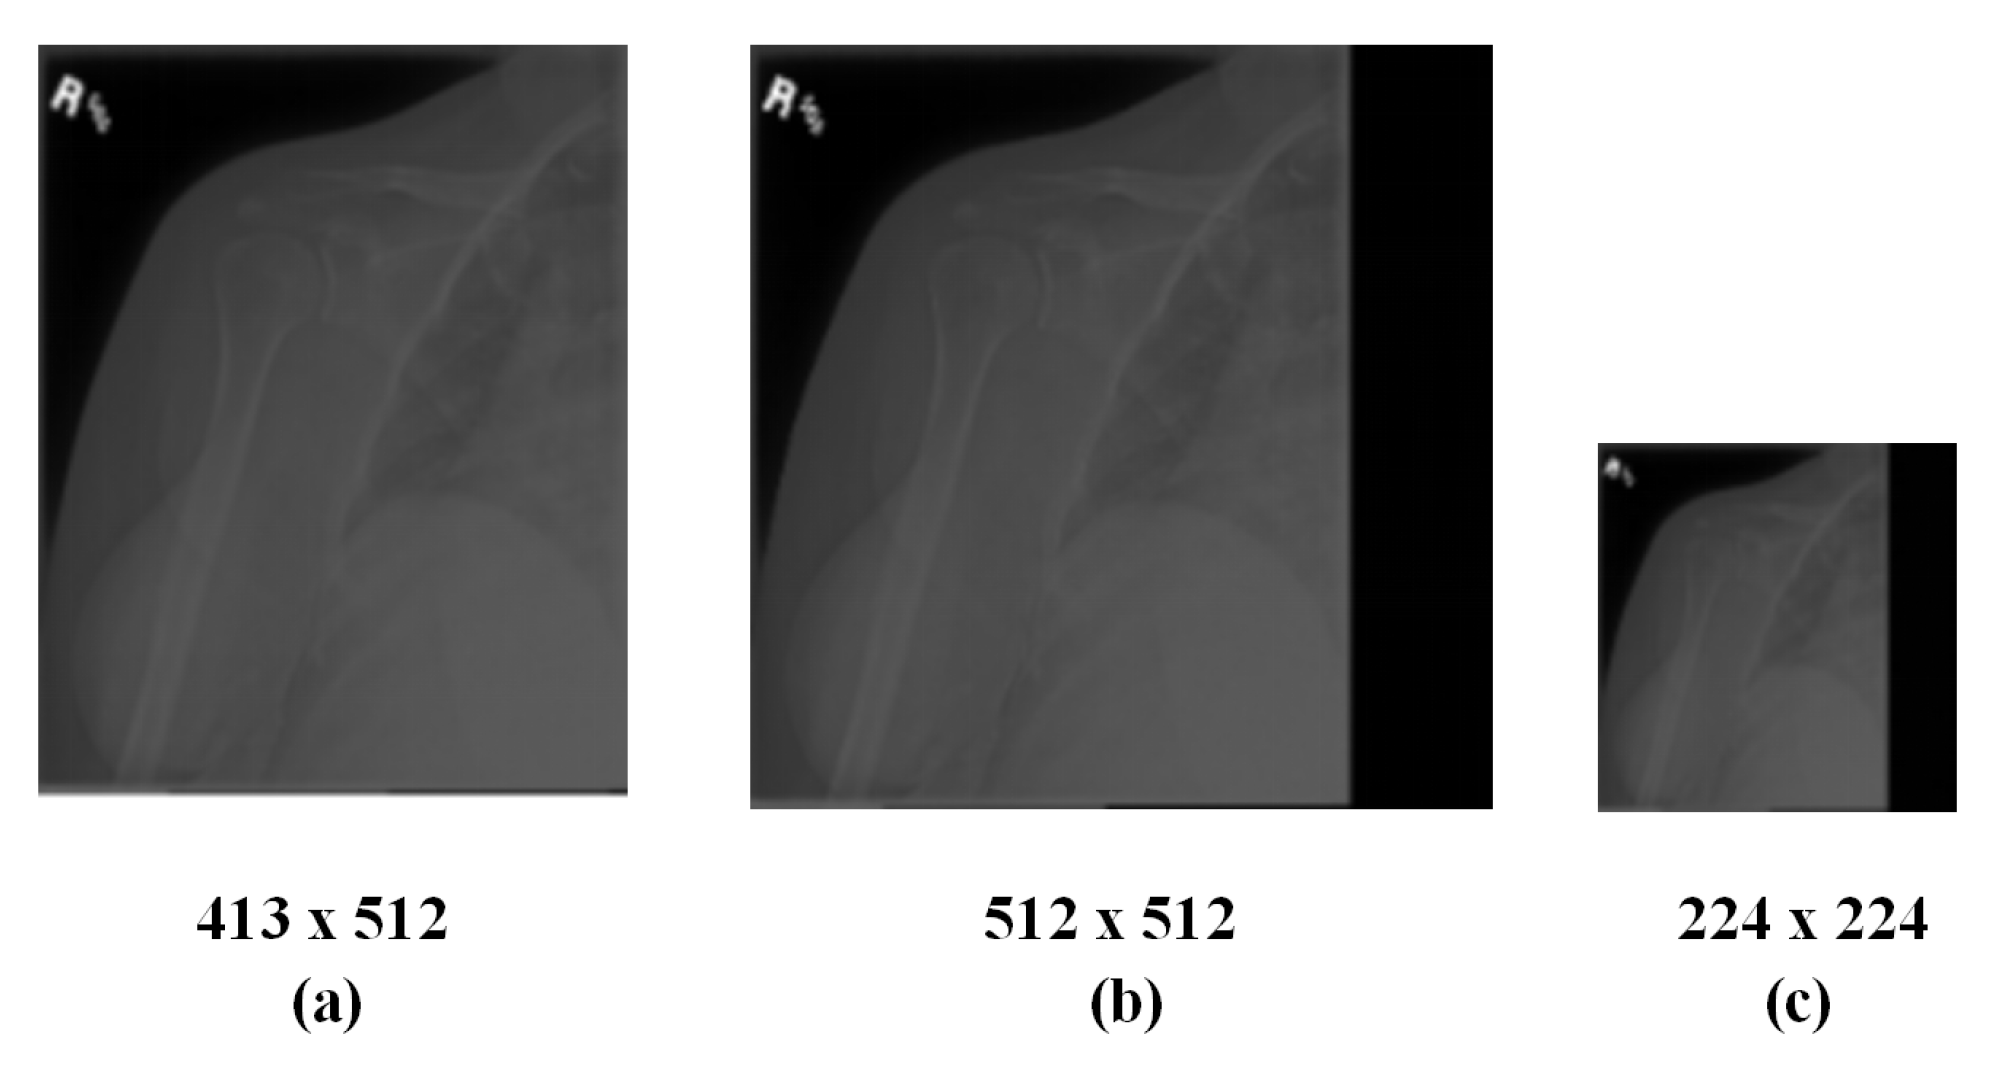

3.1. Method of Radiographs Preprocessing

- Calculate the maximum value between the width and height as L.

- Create a new square image with L as the edge and 0 as each pixel value.

- Align the original image with the top left corner of the newly created image and merge both.

- Shrink the merged image expected size.